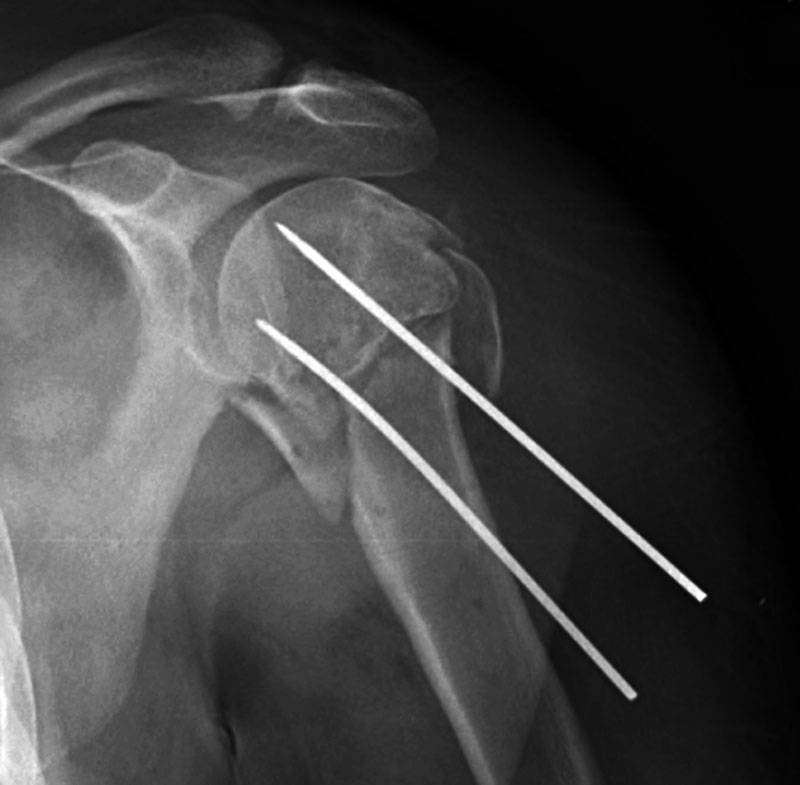

Hybrid external fixator Hybrid external fixator Ring (Ilizarov) external fixator Steinman pins in shoulder

57 year-old man with chronic fracture deformities treated by tibial and fibular osteotomies and placement of a hybrid external fixator. The fixator stabilizes a healing tibial fracture and a fibular osteotomy. From Taljanovic, 2005 From Taljanovic, 2005